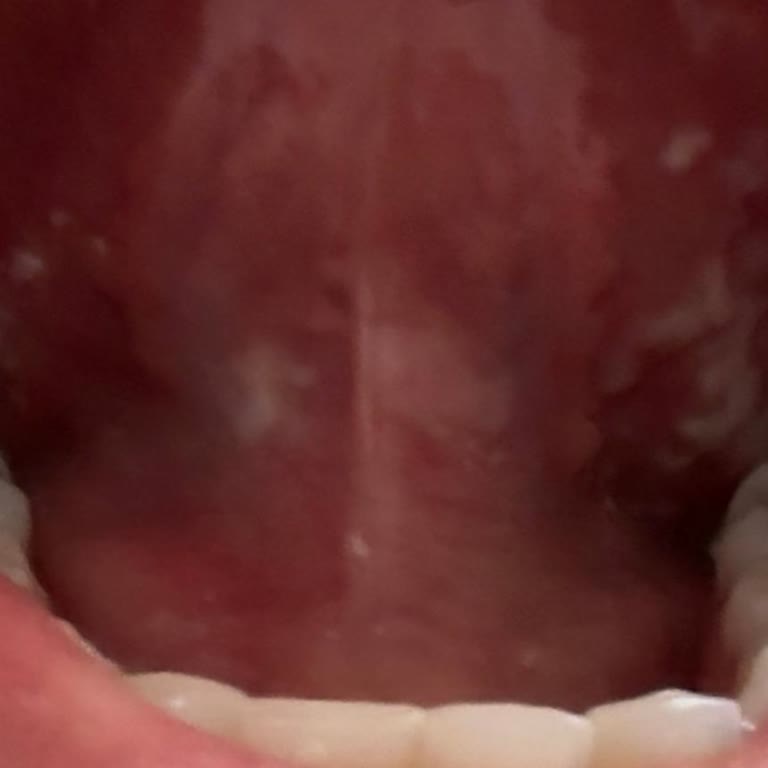

Sensodyne Hassasiyet ve Diş Eti diş macununu 1 aydır kullanıyorum ve ağzımda 1 aydır yaralar var. İlk başta vitamin eksikliği sanıp kan verdim ve vitaminden değildi. Çok korktum, başka bir sorun var diye 3 kez diş doktoruna gittim ama bir çaresini bulamadık. En son aklıma diş macunundan olabileceği ...